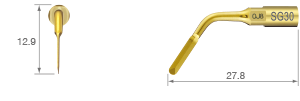

Nivelación de la cresta alveolar o escisión ósea.

• POTENCIA [SURG] 80%

• Revestimiento de TiN

• Punta con borde de espátula de tres lados

• Instrumento de un solo filo